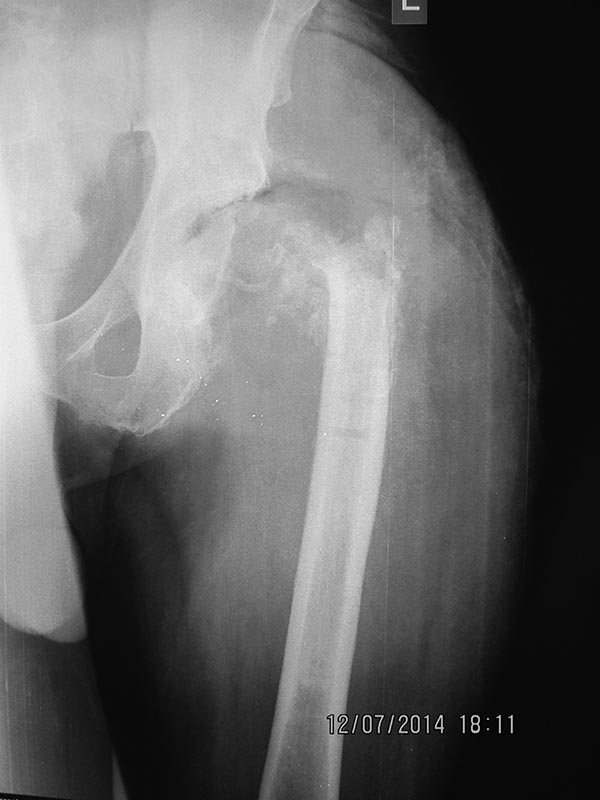

50-летний мужчина, в начале апреля по пьяни автоаврия, реанимация.

Закрытый чрезвертельный переломовывих бедра с переломом вертлужрой

впадины с нейропатией седалищного нерва. Только через 10 дней смогли

прооперировать ! Остеосинтез вертлужной впадины цепочкой АО, DHS, вывих

вправлен. На 7-й день с проксимального угла раны появилось серозное

отделяемое, через 3 дня швы с проксимальной половины раны удалены, еще

через 3 дня остальные, до фасции. Через несколько дней перешли на

вакуумирование при помощи губки и Steri-drape- а. Рана начала быстро

зажиаать, однако, экссудат стал вонючим (тяжелый сырный запах). По

анализу энтеробактер. Через 3 недели после синтеза - первая ревизия, в

голвке и вокруг имплантатов - вонючий желтый гной. Все железо и головка

удалены, дренажи, кожа ушита. Однако, промывание не удалось,

неэффективная эвакуация, швы удалены. Затем опять пара ревизий,

каждодневные перевязки, но почти каждый день гной из бедренного канала

или вертлужной впадины, хотя рана обильно гранулирует. У кого какие мнения?